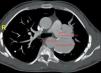

Caso clínicoJovem de 12 anos, baleado acidentalmente na face anterior do tórax (4.°‐5.° espaço intercostal), com traumatismo medular do qual resultou paraplegia. Manteve autonomia funcional, deslocando‐se em cadeira de rodas. Aos 15 anos, em consulta de rotina, foi detetado ligeiro sopro cardíaco, estando assintomático do ponto de vista cardiovascular. Aos 25 anos, apesar de não ter novas queixas, tendo‐se notado um agravamento do sopro (contínuo), foi referenciado a consulta de cardiologia. Durante o estudo etiológico detetou‐se em radiografia do tórax hipodensidade na área para‐hilar esquerda. Este achado foi estudado por TC, que revelou pseudoaneurisma da aorta torácica descendente (Figura 1), com fistulização para a artéria pulmonar esquerda (Figuras 2 e 3).